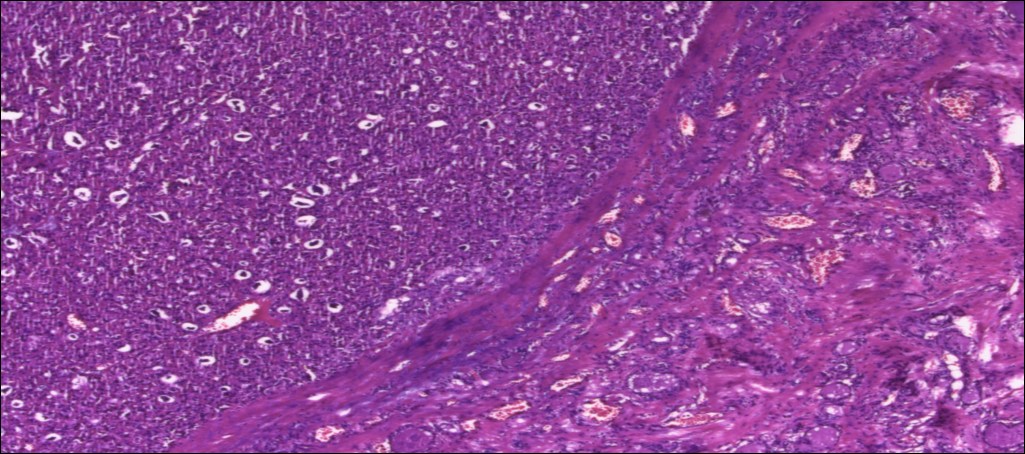

甲状腺嗜酸性细胞腺瘤

(甲状腺右叶及峡部):暗褐结节,直径6cm,包膜完整

肿物包膜完整,镜下未见明确包膜、脉管侵犯

镜下可见包膜,脉管侵犯!